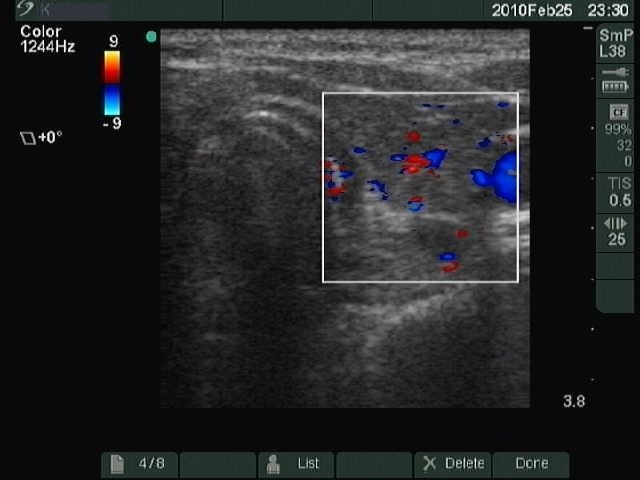

Chronic lymphocytic thyroiditis - Case 49. |

Clinical presentation: a 49-year-old woman with a newly discovered hypothyroidism (TSH 31.7 mIU/L) and a thyroid nodule in a previous sonographic report.

Ultrasonography: typical picture of Hashimoto's thyroiditis without any nodules.

Cytological report: benign Hashimoto's thyroiditis.